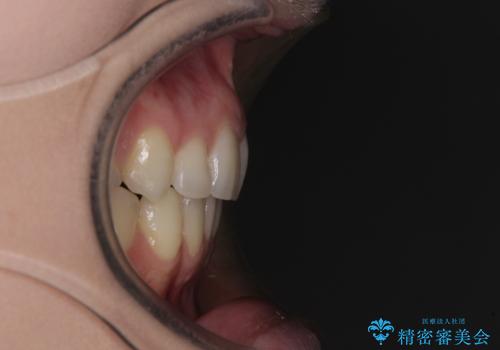

- 著しい八重歯を気にして来院された患者様です。

片側の八重歯であり上顎の正中がずれていたため、上顎左右第一小臼歯2本を抜歯して排列することとしました。